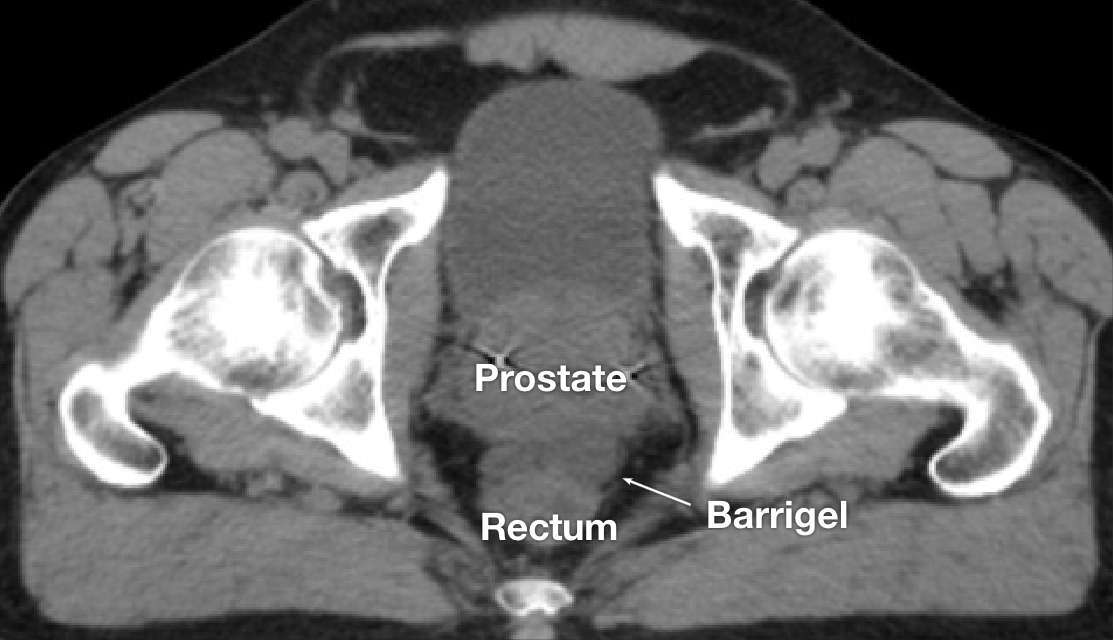

CT image courtesy of Glen Gejerman, MD

Radiation Oncologist; New Jersey, United States